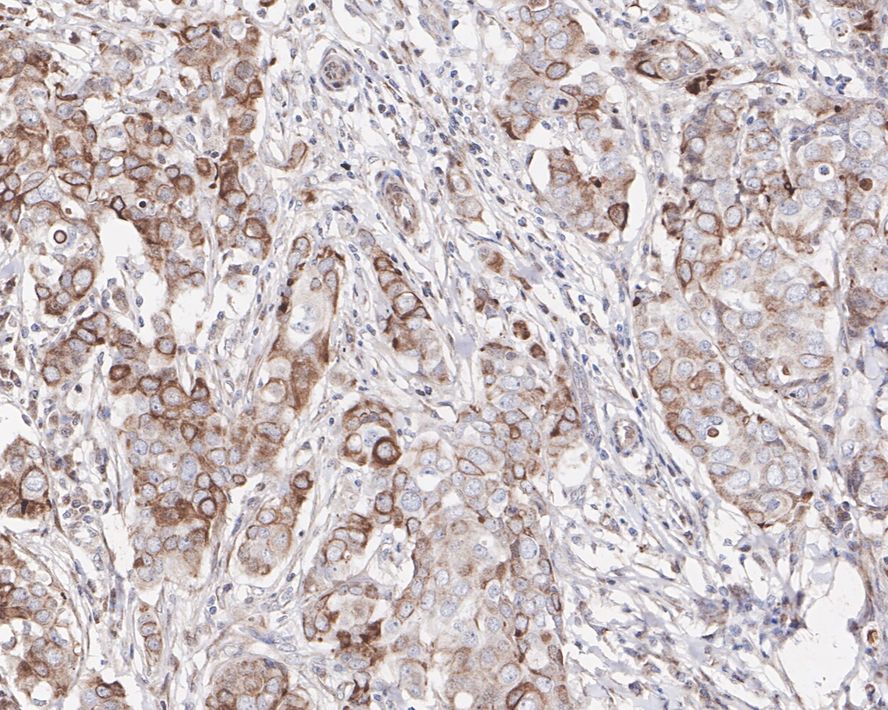

Immunohistochemical analysis of paraffin-embedded human breast carcinoma tissue with Rabbit anti-GSK3 beta antibody (HA750131) at 1/200 dilution.

The section was pre-treated using heat mediated antigen retrieval with sodium citrate buffer (pH 6.0) (high pressure) for 2 minutes. The tissues were blocked in 1% BSA for 20 minutes at room temperature, washed with ddH2O and PBS, and then probed with the primary antibody (HA750131) at 1/200 dilution for 1 hour at room temperature. The detection was performed using an HRP conjugated compact polymer system. DAB was used as the chromogen. Tissues were counterstained with hematoxylin and mounted with DPX. -